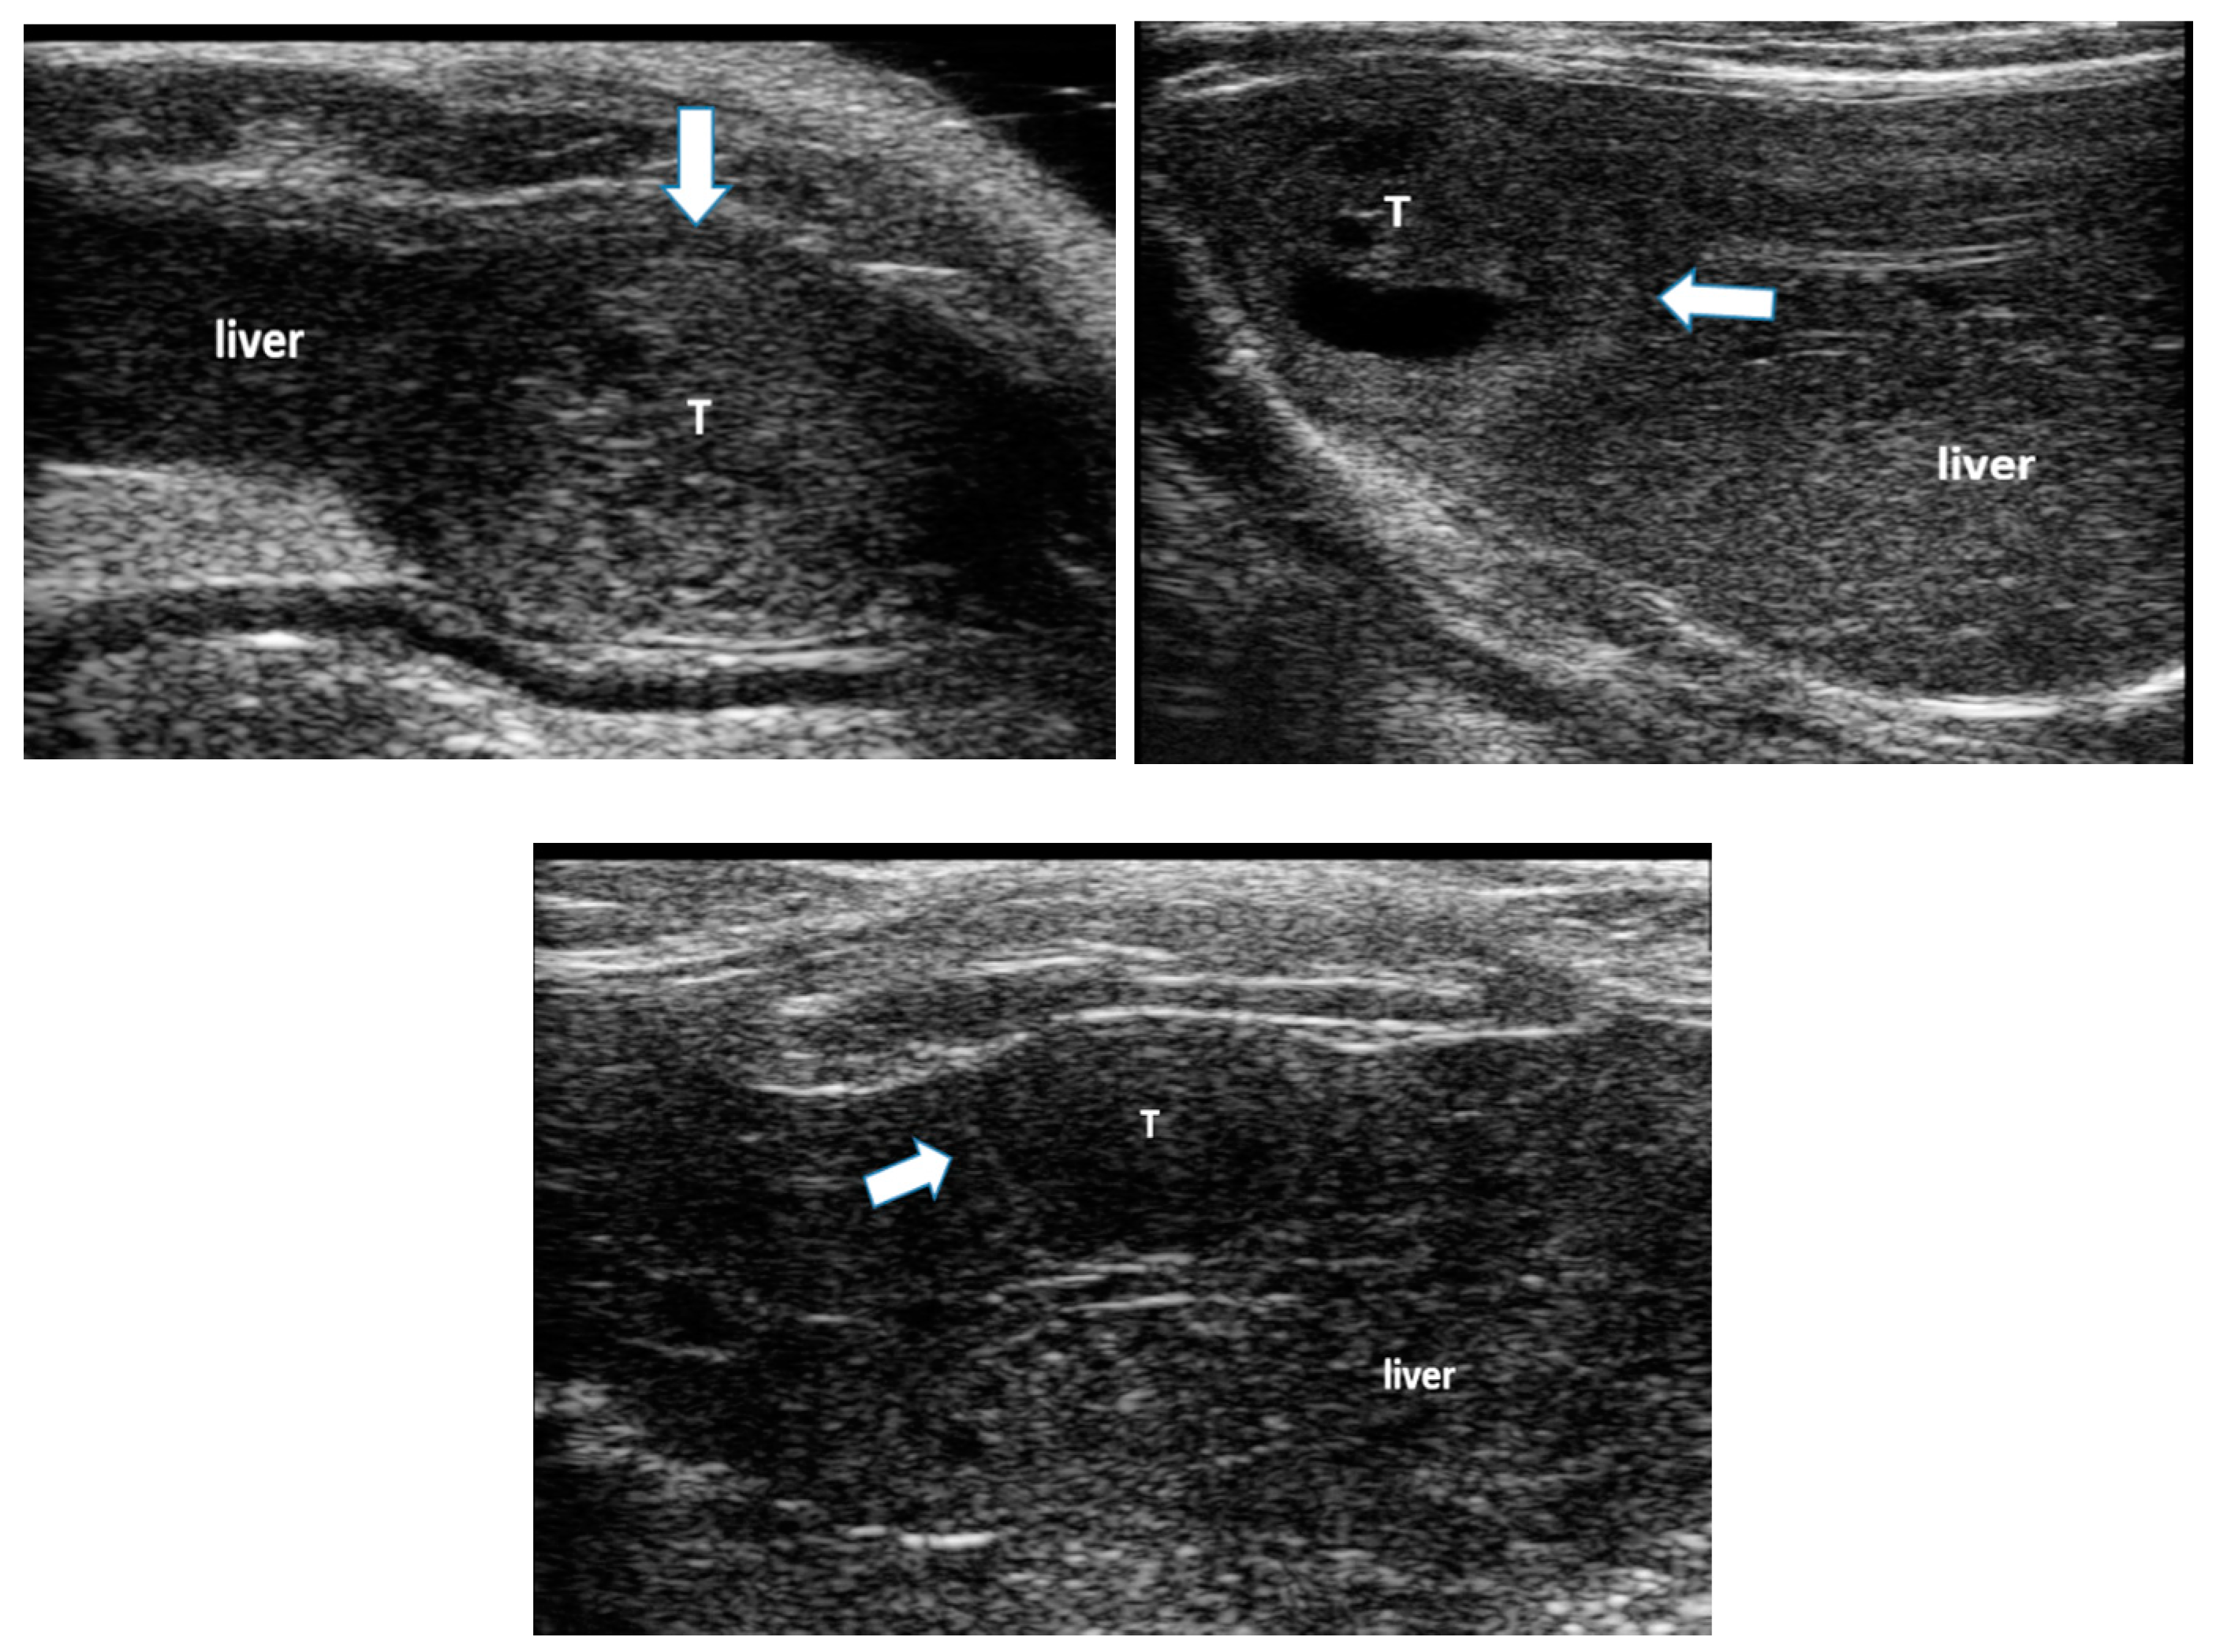

All animals developed liver disease and multiple foci of hepatocellular carcinoma (HCC), seen on B-mode ultrasound imaging (Figure 1). These tumors were associated with liver changes including increased echogenicity and coarseness of the image texture, indicating liver fibrosis and cirrhosis [22,26], ascites and hepatosplenomegaly.

Figure 1. Examples of hepatocellular carcinoma (HCC) tumors developed in the liver of rats following ingestion of diethylnitroseamine (DEN) for 12 weeks. The white arrows point to HCC tumors (T) surrounded by liver tissue. Liver tissue is hyper-echoic and coarse due to the cirrhotic changes.